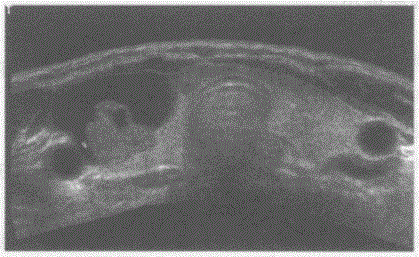

问题 请回答下图是采用哪种扫查方式获取的颈部哪一部位声像图像:

选项 A.甲状腺能量图扫查 B.甲状腺宽景超声扫查 C.甲状腺三维超声扫查 D.甲状腺造影谐波扫查

答案 B